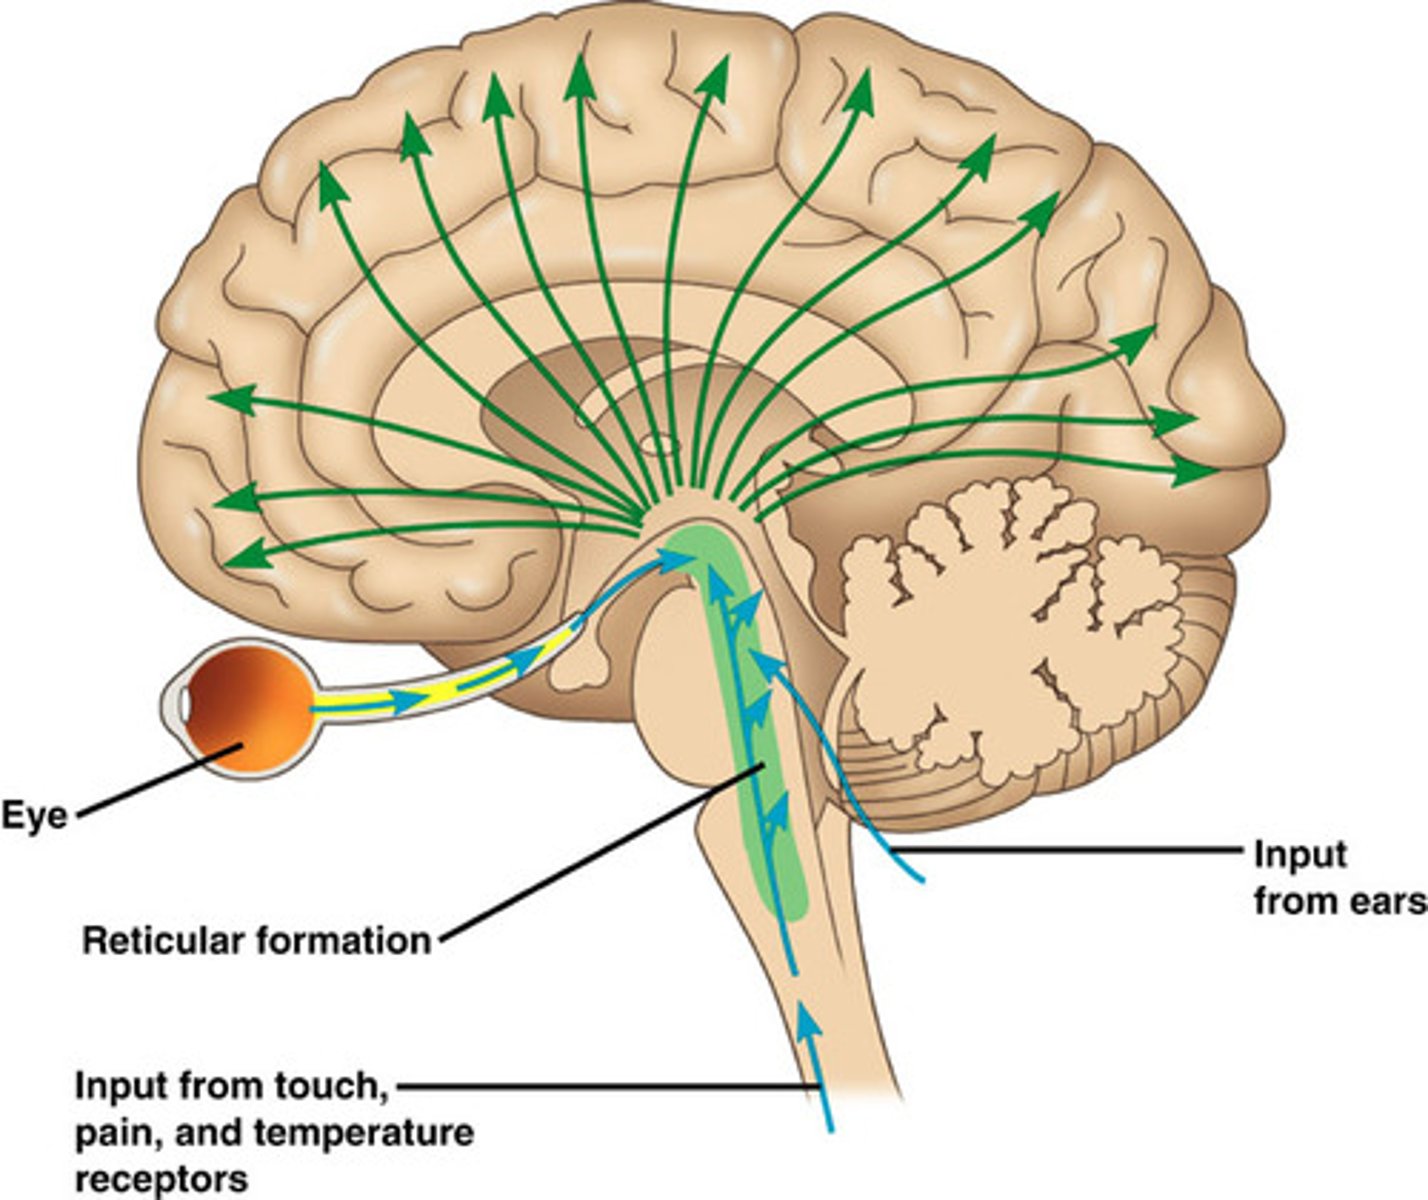

Reticular formation

nerve network - controls arousal and filters sensory information